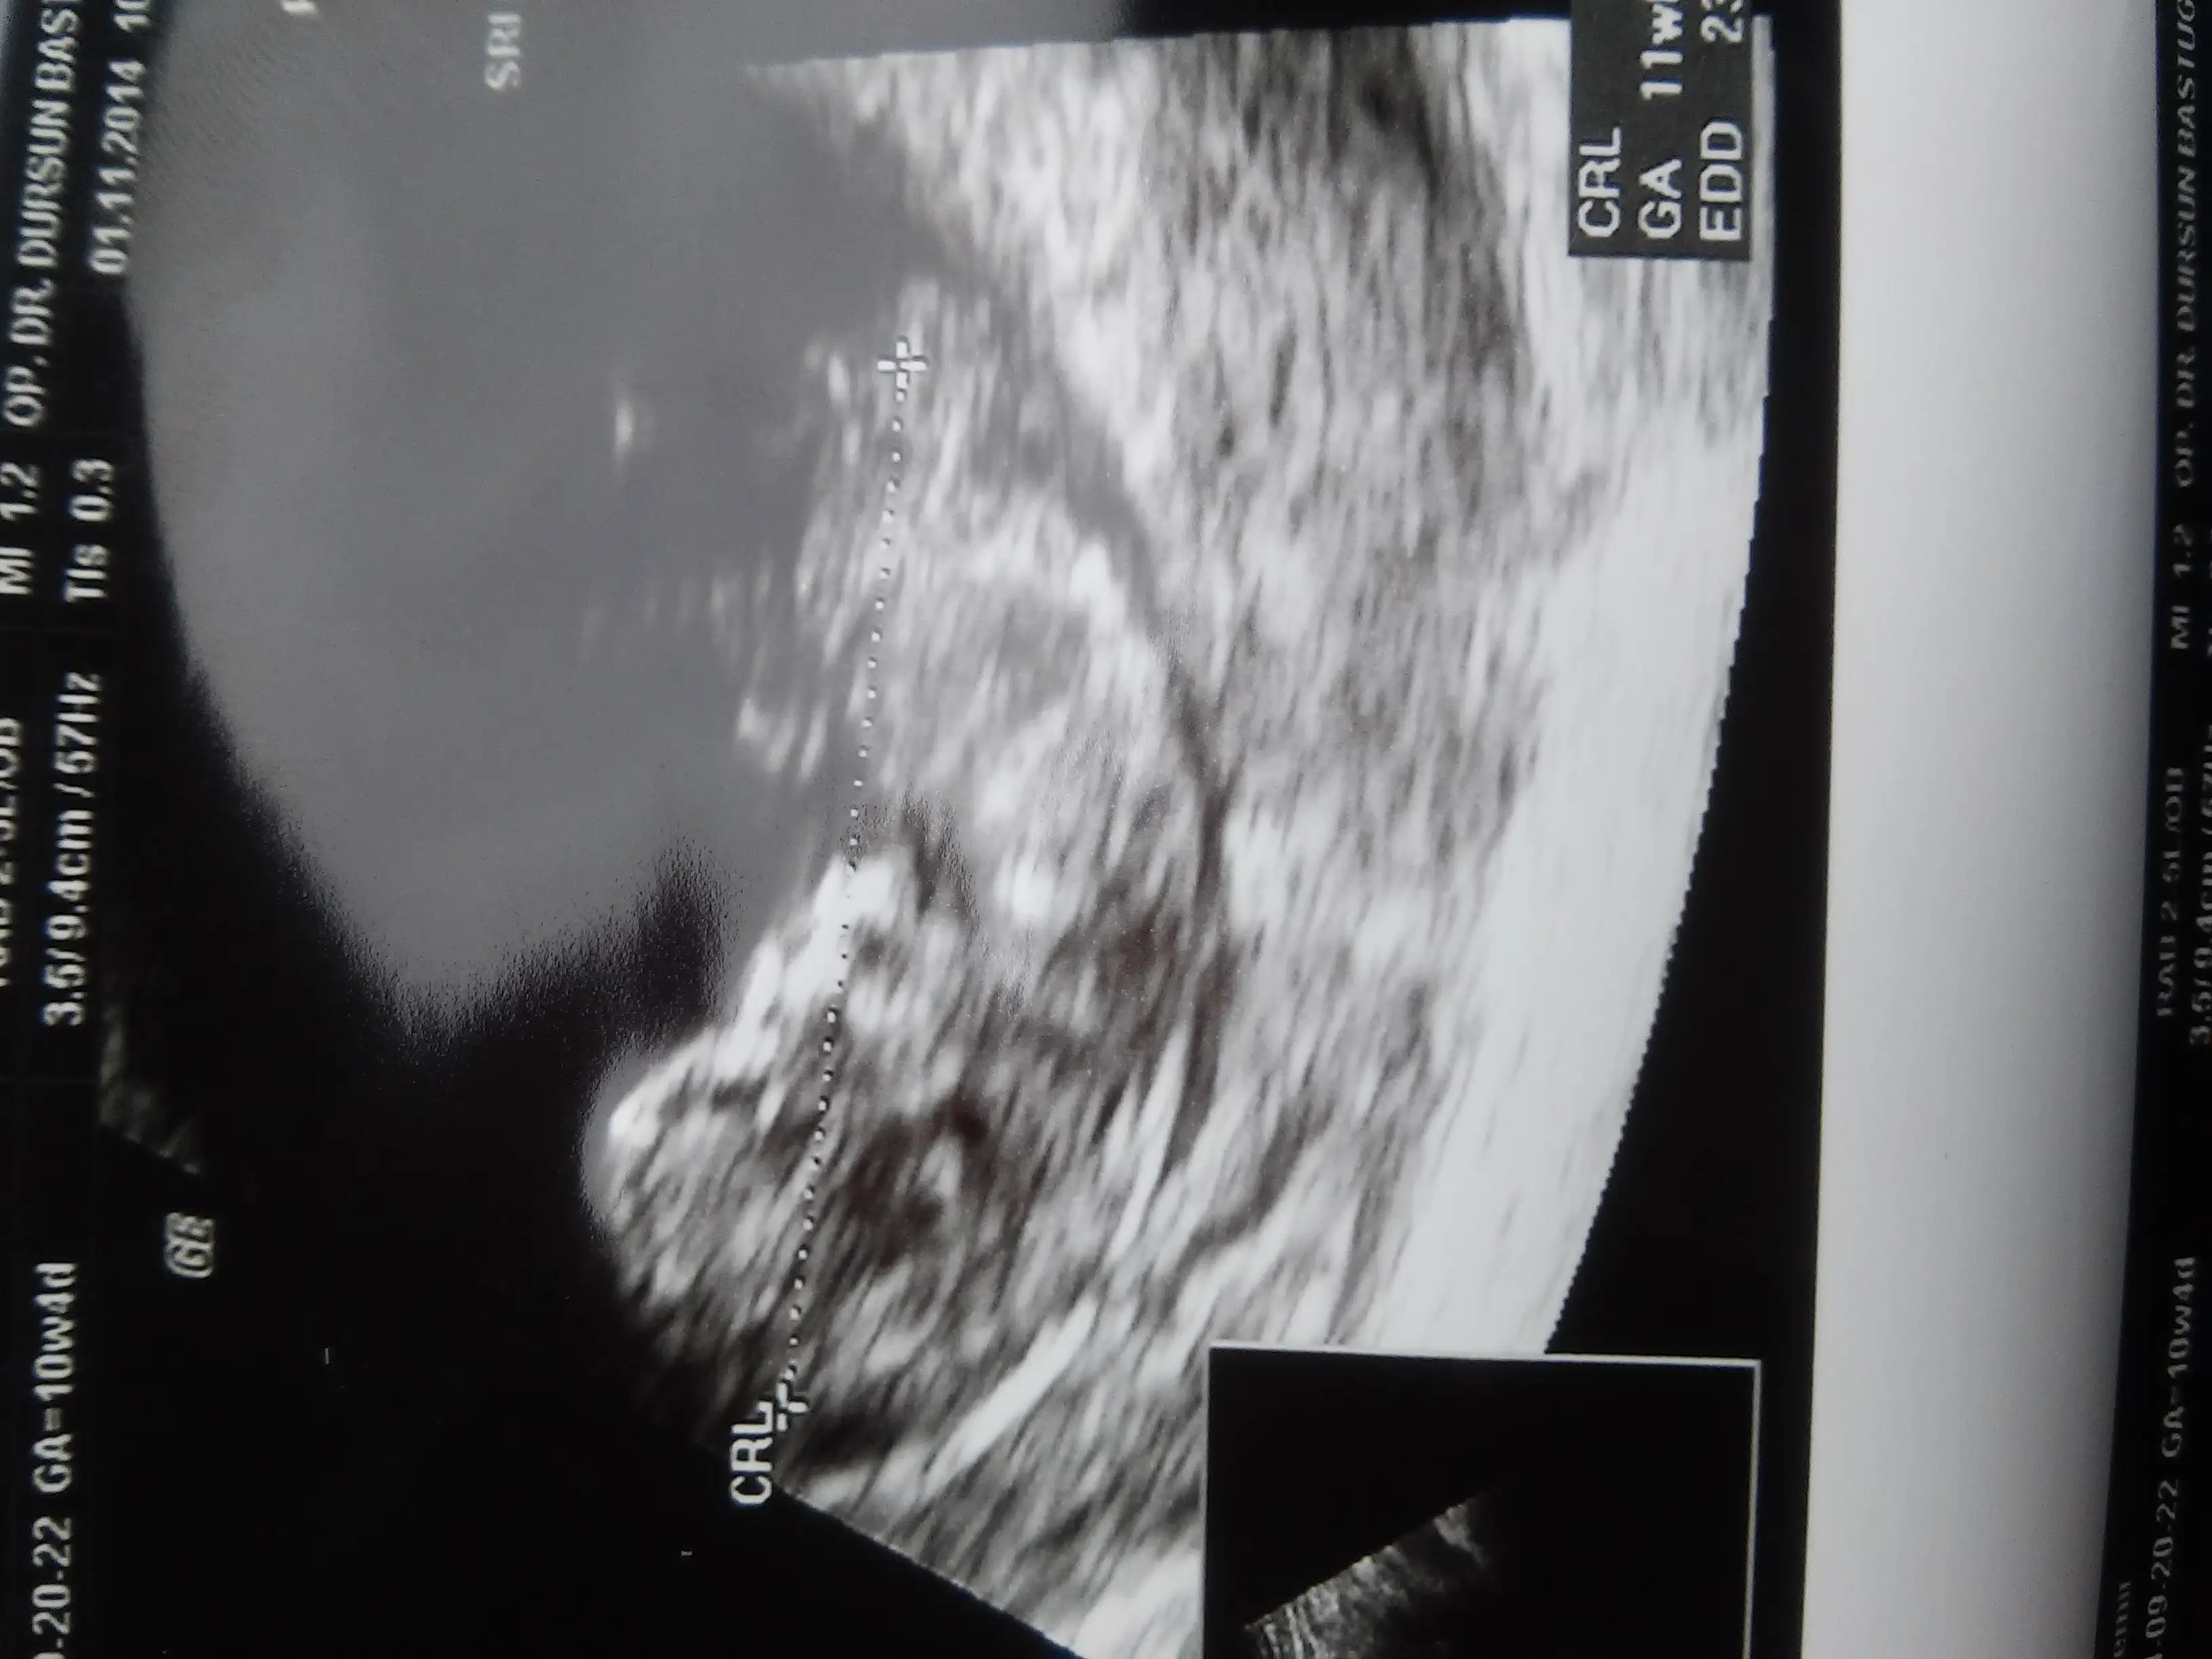

...Banada yorum yaparmisiniz lutfennn 12 haftalik hamileyim bu ultrason görüntüsünde..Eki Görüntüle 1289119